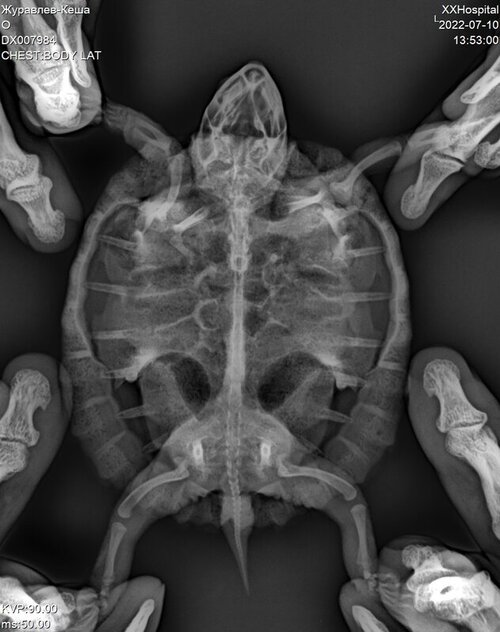

DX007984_1.JPG

DX007984_2.JPG

DX007984_3.JPG

Исправили температурный режим, УФ лампу заказали скоро должна прийти. В телеграмканале не отвечают что делать дальше. Написали про газы в целоме, что делать с ними?